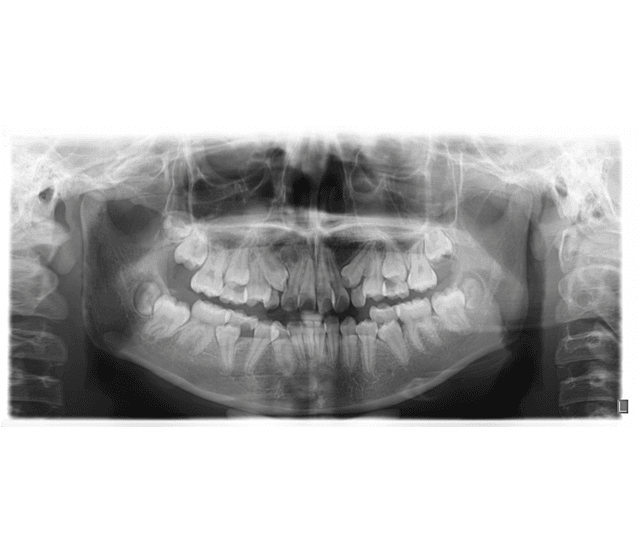

X-Rays

SmileOn clinic use the latest x-ray technology to diagnose oral health problems in a painless, non-invasive way. Though exposure to radiation can pose health risks, SmileOn uses sophisticated, portable x-ray equipment that limits this exposure to negligible levels. SmileOn clinics also use lead aprons and lead thyroid collars to protect doctors and patients from radiation. The principle directs medical establishments to identify and use ways to minimize the exposure of medical personnel, patients and clinical staff to radiation.